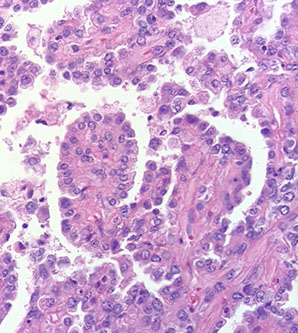

Invasive mucinous AC (formerly mucinous BAC)

Invasive mucinous adenocarcinoma

- formerly known as mucinous bronchoalveolar carcinoma (BAC), but renamed in the new classification

- multiple nodules, >3 cm

Has major clinical, radiologic, pathologic and genetic differences from the tumors formerly called nonmucinous BAC

- in particular, has a very strong correlation c KRAS mutation, whereas nonmucinous AC likely have EGFR mutations

- in majority of cases has an invasive component, and tend to be multifocal

IHC: (+) CDX-2 (sometimes(

- neg: TTF-1 (0-17% pos in studies)

Px: Not good, commonly recurs after resection